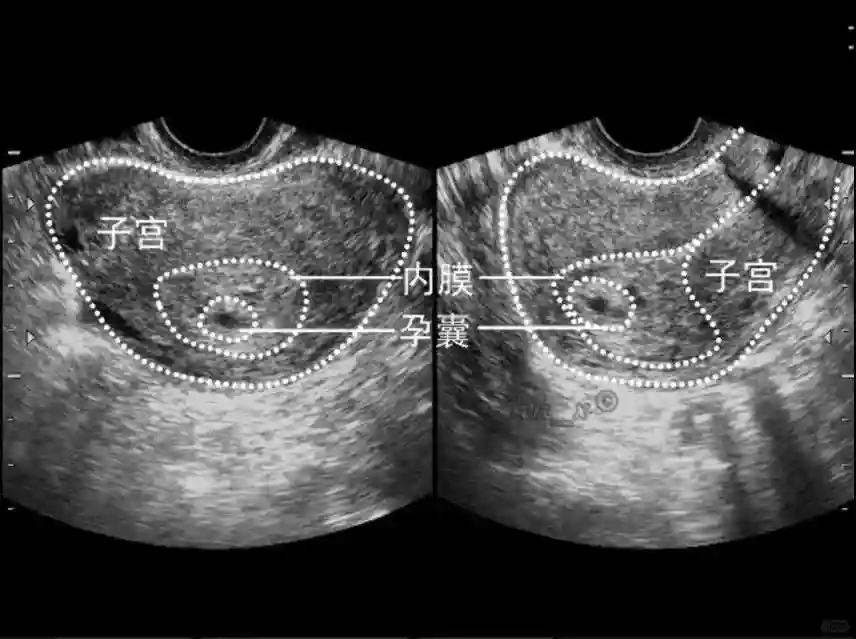

1??妊娠囊:早期妊娠囊:正常妊娠囊位于宫腔上段,表现为宫腔内圆形或椭圆形的无回声区,周边为完整的、厚度均匀的强回声环,强回声环厚度≥2mm,强回声是妊娠绒毛的回声,随着妊娠囊的增大,形成特征性的“双环征” ,10周以后消失。正常的妊娠囊增长速度是平均 1 mm /d。

2??卵黄囊:是妊娠囊内第一个解剖结构,直径<7mm。表现为小环状,中央为无回声,囊壁薄,内透声好。卵黄囊位于胚胎旁胚外体腔内。卵黄囊通常在孕5-6周时出现,5-10周稳步增长,一般不超过7mm,至12周消失。妊娠囊的大小与卵黄囊之间有一定关系,妊娠囊平均直径> 8 mm 时,经阴道超声均应显示卵黄囊,妊娠囊平均直径> 18 mm 时,经腹超声均应显示卵黄囊。